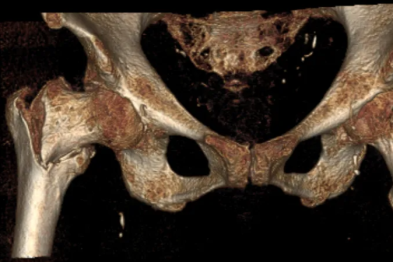

强直 20 年,他脊柱脆如玻璃!我院数字化精准外科技术让「最危险的骨折」有了安全解法